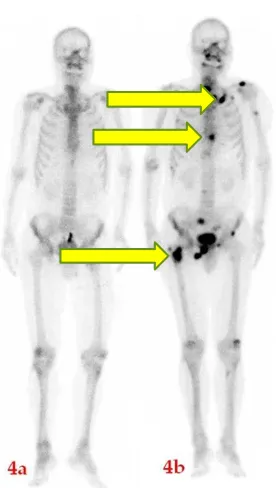

骨扫描(2024-12-06)

1. 前列腺右叶病变伴核素摄取增高,符合恶性病变影像特征,考虑前列腺癌,累及邻近右侧精囊腺;

2. 右侧股骨头及胸椎及第二肋局限性核素摄取增高,考虑转移性病变,建议定期复查。